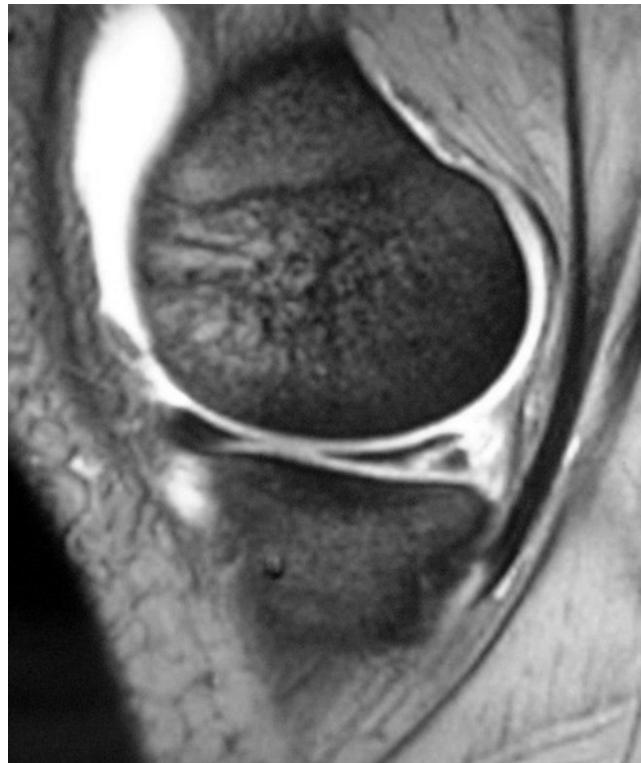

Imaging

Question: What is your finding?

Additional Case Questions

Questions for discussion:

- What is the diagnosis?

- What is the sign called? pocket handle

- What is the treatment?